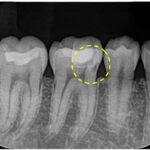

根の先の膿が大きく、歯茎も腫れている状態でした。過去の根管治療ではラバーダムは使用されておらず、根管充填の質もPoorであることから、再根管治療を行うことになりました。

6ヶ月後の経過観察時には初診時の噛んだ時の鈍痛は消失していました。レントゲン、CTにて、根尖部の明瞭な骨の回復が認められ、治療がうまく奏功していることが確認できました。